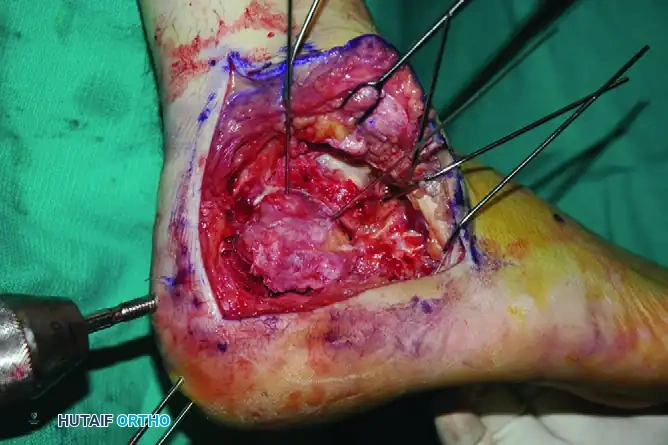

Step 4: Posterior Facet Reduction

With the calcaneus now out to length and the varus corrected, turn your attention to the intra-articular depression of the posterior facet.

- Elevate the depressed articular fragments of the posterior facet.

- Reduce them anatomically to the intact medial piece (sustentaculum tali).

- Hold the articular reduction with provisional subchondral K-wires.

- Radiographic Verification: Obtain intraoperative fluoroscopic views (Broden’s views, lateral, and axial) to assess the overall reduction, ensuring no articular step-off remains and that the hardware does not penetrate the subtalar joint.

Step 5: Defect Management

Elevating the severely impacted posterior facet often leaves a large void in the cancellous bone of the calcaneal body (the neutral triangle).

* If excellent stability of the fracture and secure internal fixation are achieved, this defect may be accepted and left empty, as it will fill with hematoma and eventually consolidate.

* Alternatively, structural autograft (iliac crest), allograft, or osteoconductive bone cement (calcium phosphate) can be utilized to fill the void and provide subchondral support, particularly in highly comminuted fractures or osteoporotic bone.

INTERNAL FIXATION STRATEGY

Following provisional K-wire fixation, definitive rigid internal fixation is applied.

Sustentacular Lag Screw Fixation

The cornerstone of calcaneal fixation is securing the lateral fragments to the intact medial sustentacular fragment.

* Insert small cortical lag screws (3.5 mm) from lateral to medial, directed into the sustentacular fragment.

* Trajectory: The screws should be aimed slightly plantar and anterior, targeting the medial malleolus, to ensure they capture the dense bone of the sustentaculum without breaching the medial cortex and endangering the flexor hallucis longus (FHL) tendon or the neurovascular bundle.